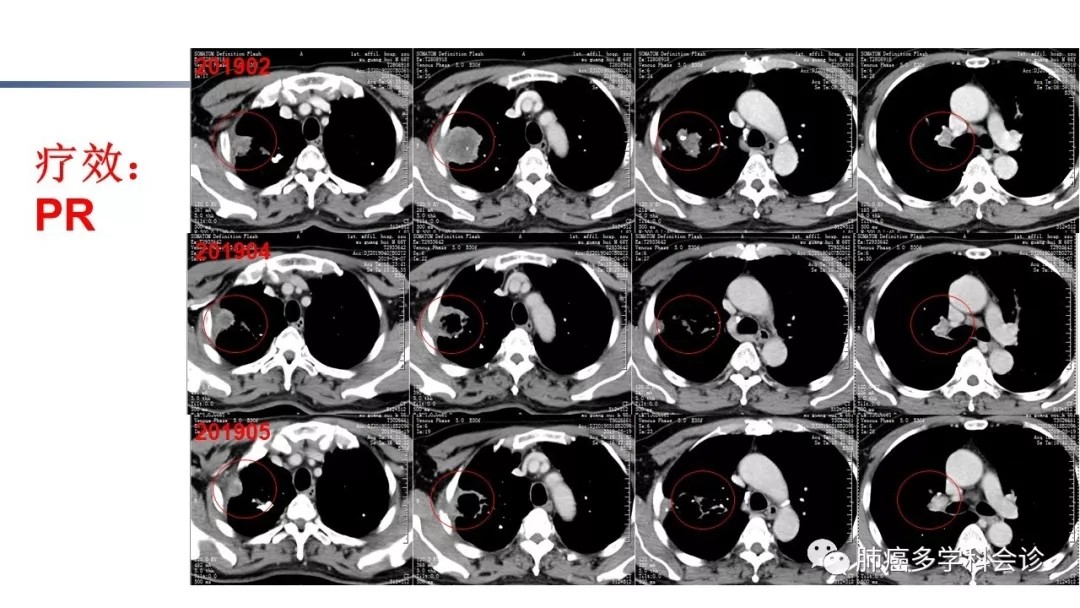

恒瑞PD-1/PD-L1抗体治疗晚期肺癌临床研究分享

讲者:郑州大学第一附属医院 张慧娴 博士